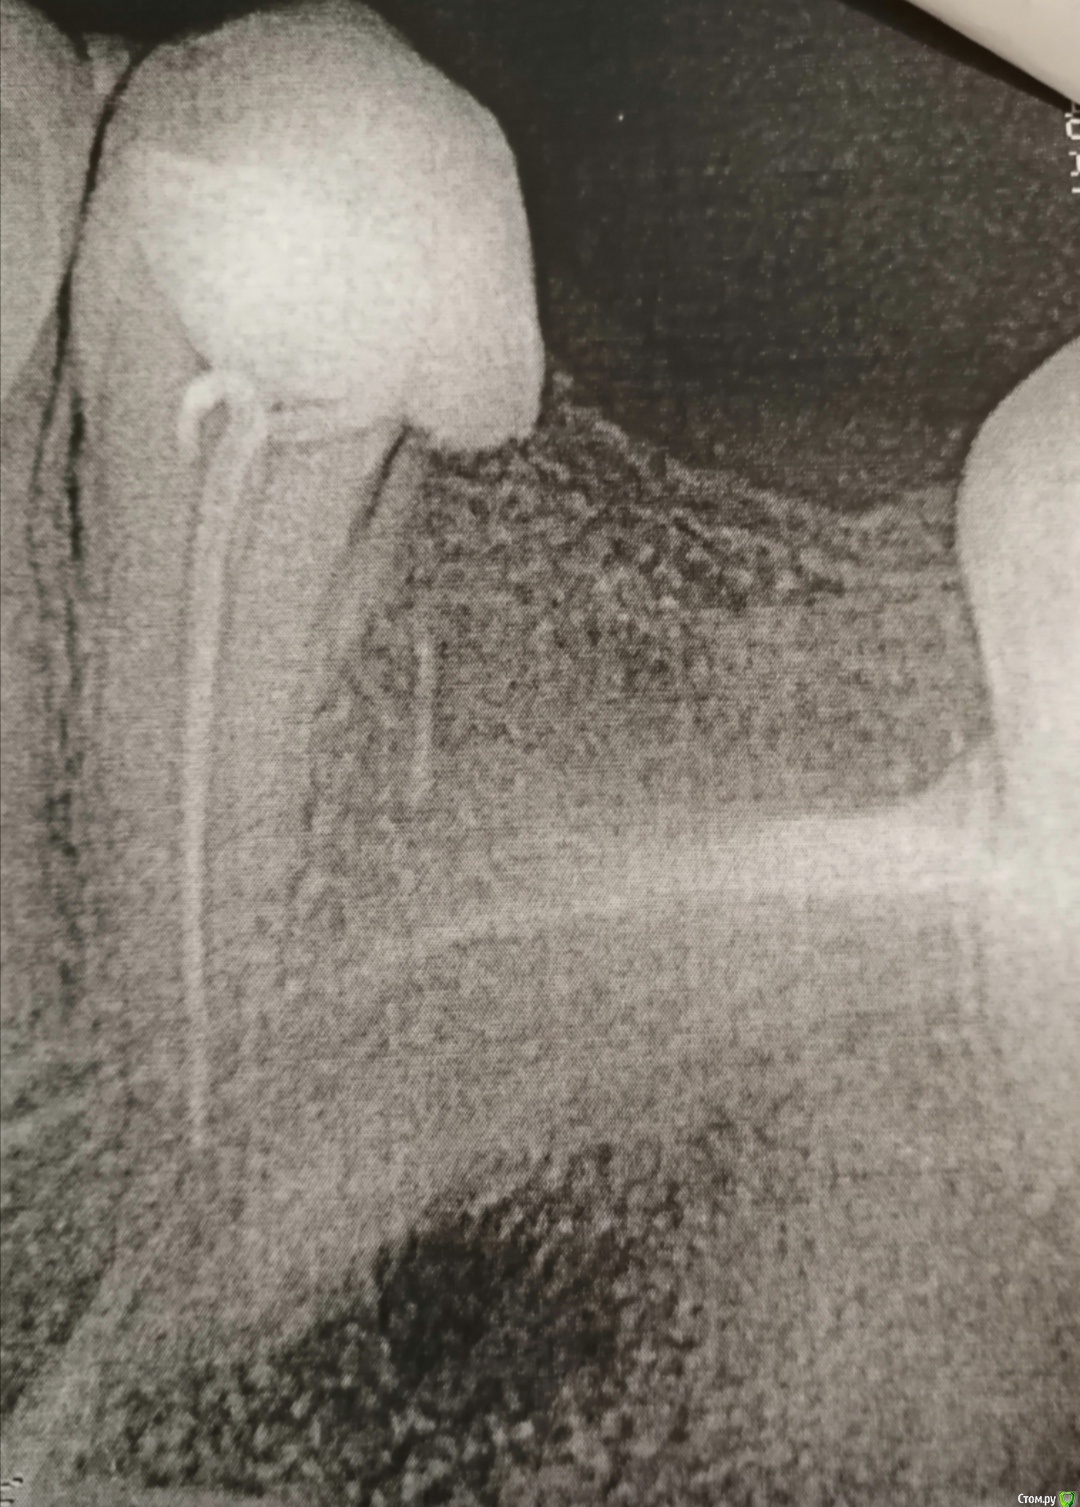

Прохожу лечение зуба, он виден на снимке, рядом удалённый зуб, примерно около года. И и на снимке видно то ли какой то осколок то ли что, расшифруйте пожалуйста. Неужели мне когда удалили зуб, что то оставили там.